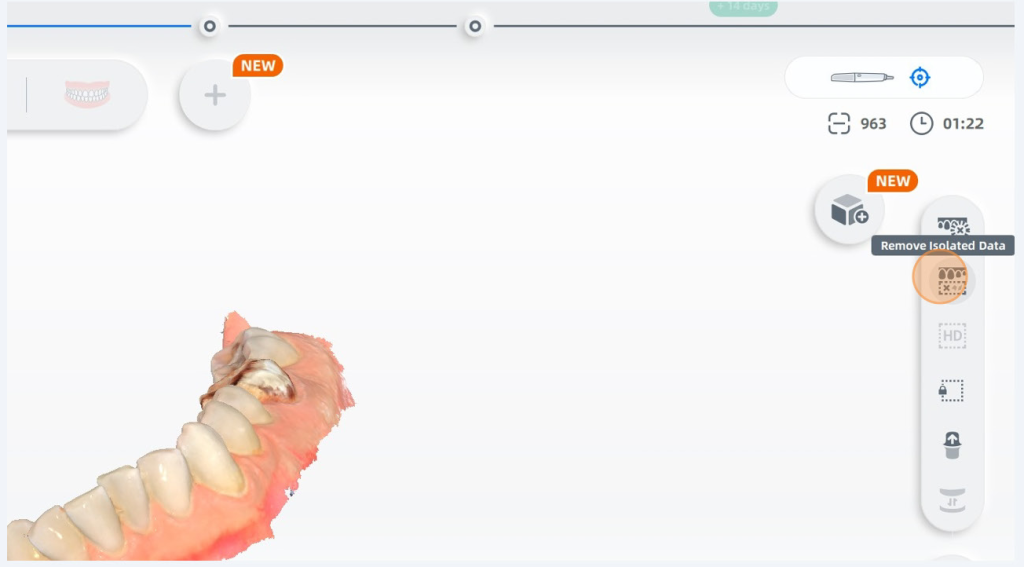

My scan had some artifacts from scanning without AI on, I can remove it easily by clicking the remove isolated data button.